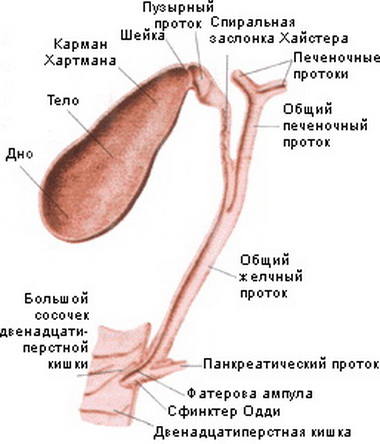

Анатомия и особенности Гартманова кармана желчного пузыря